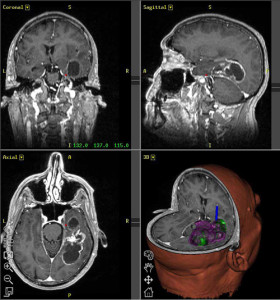

glioblastoma

La sopravvivenza a una delle forme piu’ aggressive di tumore al cervello e’ raddoppiata negli ultimi 30 anni. Nuovi dati dimostrano che la meta’ dei pazienti e’ ancora viva dopo la diagnosi, fatto impensabile una generazione fa.